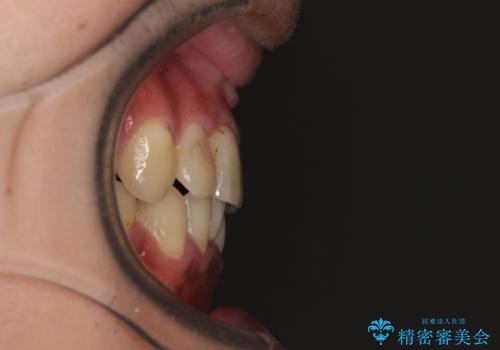

重なって磨きにくい上下の前歯 ワイヤー装置での抜歯矯正

- 前歯のデコボコを改善したいと来院された患者様です。

口元の突出感はないものの、上顎前歯のデコボコが著しかったため、上下顎左右小臼歯4本を抜歯することとしました。

上下の正中位置を改善するため、右下は第一小臼歯を、その他は第二小臼歯を抜歯することとしました。